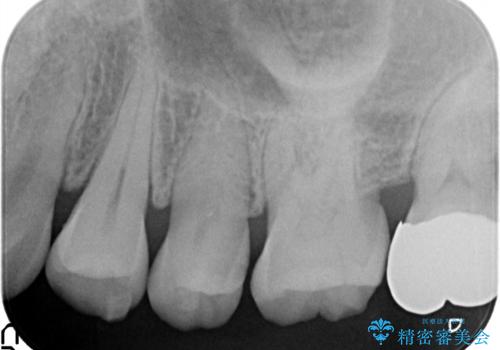

虫歯の治療。ゴールドインレーによる治療

- 定期検診にて、虫歯を発見した患者様です。

長期に安定した治療を希望されたためPGAインレーにて修復治療を行っております。

ゴールドインレーは適合が良く、割れることもないため、長期的に安定した治療法となります。